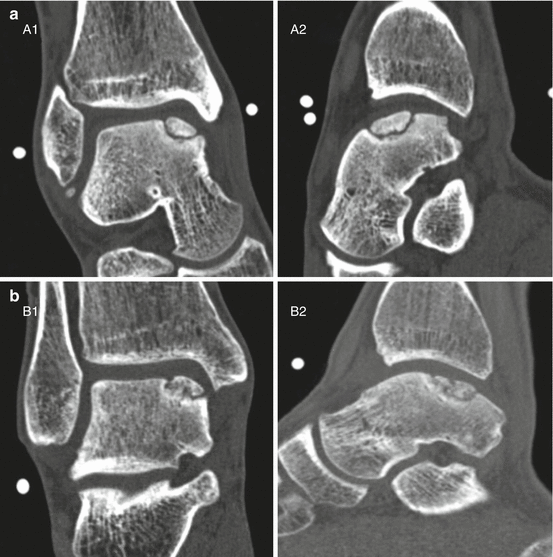

Exercises for an osteochondral lesion of the talar dome. Osteochondral lesions of the talus are focal injuries to the talar dome with variable involvement of the subchondral bone and cartilage which may be caused by a traumatic event or. These lesions are not only.

Osteochondral Lesions of the Talus Foot & Ankle Orthobullets

Osteochondral defects of the talus with a focus on plateletrich plasma